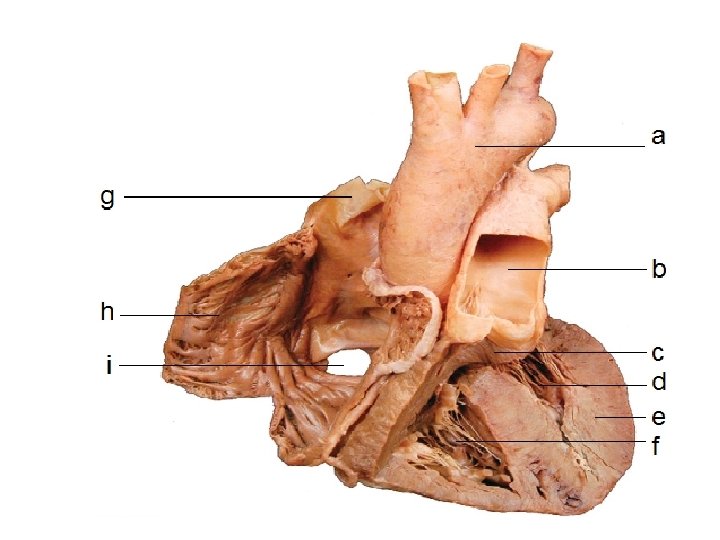

Internal Structure of the Heart • The heart has four chambers: the left and right atria (1 atrium) and the left and right ventricles. • The following diagram is the internal structure of the heart.

• Remember that the left side (RED) accepts and pumps out oxygenated blood. • The right side of the heart (BLUE) accepts and pumps out deoxygenated blood.

VALVES IN THE HEART • There are four valves in the heart: – Two semilunar valves, (one in each side of the heart). – Two atrioventricular valves (one each found between the atria and ventricles on both sides of the heart). – The function of the valves in the heart are to direct the flow of blood in only one direction.

Path of Oxygenated Blood • Pulmonary vein left atrium • Through mitral valve down into the left ventricle. • The ventricle then contracts forcing the mitral valve closed and opening the semilunar valve. • The blood then flows up into the aorta and around the body.

Path of Deoxygenated blood • Vena cava right atrium • Through tricuspid valve right ventricle. • Ventricle contracts, tricuspid valve closes, semilunar valve opens. • Blood flows to the pulmonary artery lungs.